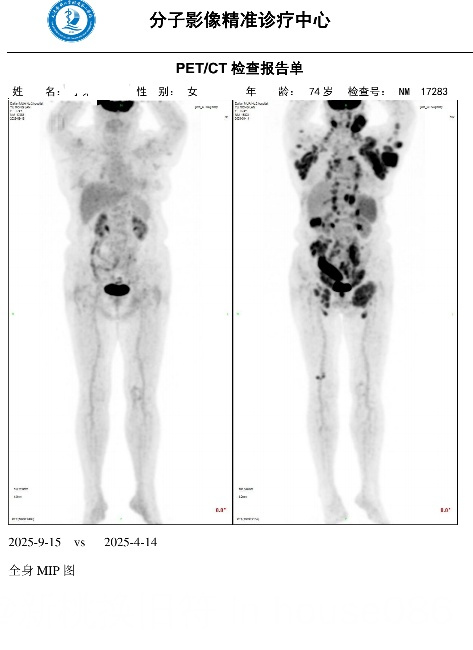

四个周期后的pet我放在下方。